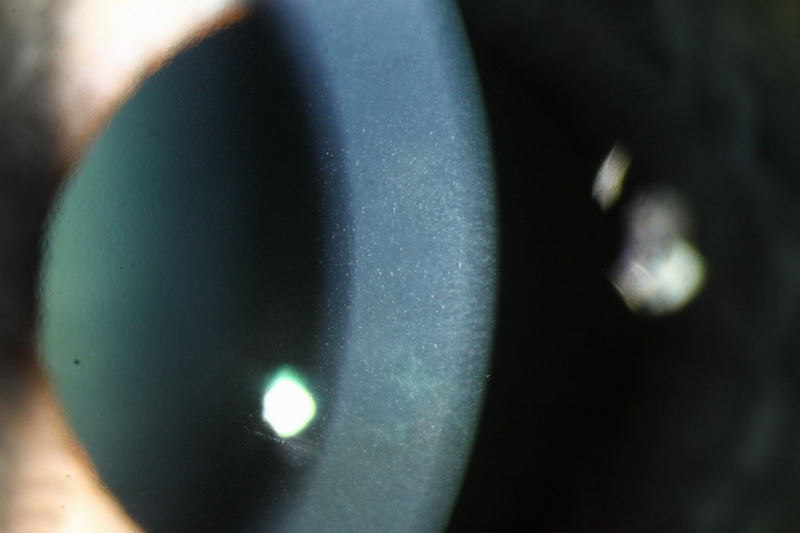

В 1911 г. Альфред Фогт подробно описал биомикроскопическую картину начальных клинических проявлений заболевания и предложил термин «cornea guttata» для описания характерных эндотелиальных изменений роговицы в виде капель или выпячиваний, которые при увеличении напоминают вид «булыжной мостовой» или «запотелого стекла». Считается, что cornea guttata служит основным клиническим признаком ДФ и является обязательной находкой при биомикроскопическом исследовании задних слоев роговицы. В то же время немаловажным является тот факт, что cornea guttata может носить посттравматический или поствоспалительный характер, являясь при этом признаком вторичной недостаточности монослоя эндотелиальных клеток.

Эндотелиальную дистрофию Фукса характеризует асимметричный, двусторонний, медленно прогрессирующий отек роговицы, встречающийся, как правило, у пожилых людей (поздняя форма). Первопричиной этого отека является медленно прогрессирующее формирование каплевидных образований (гутт) между эндотелием роговицы и десцеметовой мембраной. При ранней форме заболевания наросты (гутты) на десцеметовой мембране небольшого размера, округлые, проецируются на центр эндотелиальной клетки, в то время как при наиболее распространенной поздней форме эндотелиальной дистрофии Фукса наросты крупнее, с острыми вершинами и первично располагаются по краю эндотелиальной клетки. Каплевидные наросты («cornea guttata») могут также иметь бородавчатую или грибовидную форму. Считается, что эти патологические структуры, состоящие из базальной мембраны и фибриллярного коллагена, производят дистрофически измененные эндотелиальные клетки.

Таким образом, на самых ранних стадиях эндотелиальной дистрофии Фукса образуются гутты, которые определяются при осмотре на щелевой лампе как безрефлексные (неотражающие) точки, видимые в зеркальном изображении эндотелия, или как втянутые частицы — при обратном освещении. Существуют два основных варианта первичной «cornea guttata»:

I стадия, именуемая «сornea guttata», как правило, развивается на 4-м или 5-м десятилетии жизни. Эндотелиальные клетки начинают продуцировать наросты (гутты) каплевидной, бородавчатой, грибовидной или наковально подобной формы. Эти наросты, сформированные из коллагена с увеличенными пространствами между волокнами, выступают в переднюю камеру и впоследствии могут погружаться в отложения заднего коллагенового слоя десцеметовой мембраны. Как правило, гутты появляются в центральной зоне роговицы. Постепенно утолщения десцеметовой мембраны становятся видны при боковом (тангенциальном) освещении. Пигмент, фагоцитируемый эндотелиальными клетками, образует географический рисунок. Число гутт постепенно увеличиваются, они сливаются друг с другом и распространяются от центра к периферии, в результате чего внешний вид десцеметовой мембраны напоминает металлическую крошку. Это патологическое состояние.

При прогрессировании «cornea guttata» эндотелиальный слой постепенно истончается и разрушается. Межклеточные промежутки расширяются, связующие клетки и контактные взаимодействия исчезают. Развиваются десмосомальные соединения клеток, что может приводить к фибробластной метаплазии. Несмотря на потерю соединительных комплексов и уменьшение количества клеток эндотелия, на ранних стадиях заболевания функции насоса компенсаторно могут быть значительно увеличены. Пациенты обычно не предъявляют жалоб на данной стадии. Только некоторые из них замечают, что качество зрения при сохраненной высокой остроте несколько изменилось. Обследование эндотелия под щелевой лампой и зеркальная микроскопия эндотелиального слоя помогают установить диагноз. Легкая или умеренно выраженная «cornea guttata» может пребывать в таком состоянии в течение многих лет без ущерба для зрения пациента.